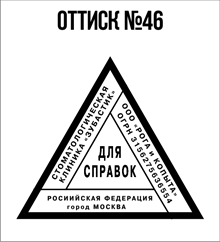

- Первое – это огромный выбор клише, то есть изображений будущей печати. Посмотрите, пожалуйста, чуть выше у нас на данной странице сайта имеется галерея изображений. Вы можете выбрать любое понравившееся Вам и сделать заказ;